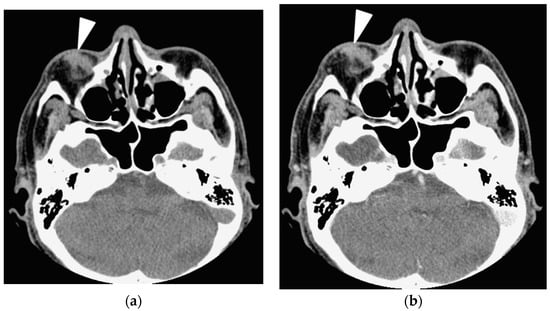

In contrast, tumors involving the extraconal, conal or intraconal space, lacrimal sac, optic nerve, extraocular muscle tendon, infraorbital nerve, preseptal space and presence of sinusitis and bone remodeling were ineffectual to differentiate IgG4-ROD from orbital lymphoma (Figure 1 and Figure 2; all p > 0.05, Fisher’s exact test). Two IgG4-ROD patients and 6 OL patients had a solitary tumor involving the preseptal space (Figure 2).

Figure 2. A 66-year-old man with orbital lymphoma shows a painless solitary lesion at the right lower eyelid. (a) Axial precontrast CT image shows a small nodule with an irregular border and homogeneous density involves the preseptal space of the right lower eyelid (arrowhead). Precontrast CT Hounsfield unit scale (CTHU) of the nodule is 57; (b) Axial postcontrast CT image shows the nodule demonstrates homogeneous enhancement (arrowhead). Postcontrast CTHU of the nodule is 68. Serum IgG4 level of the patient is 44.3 mg/dL.